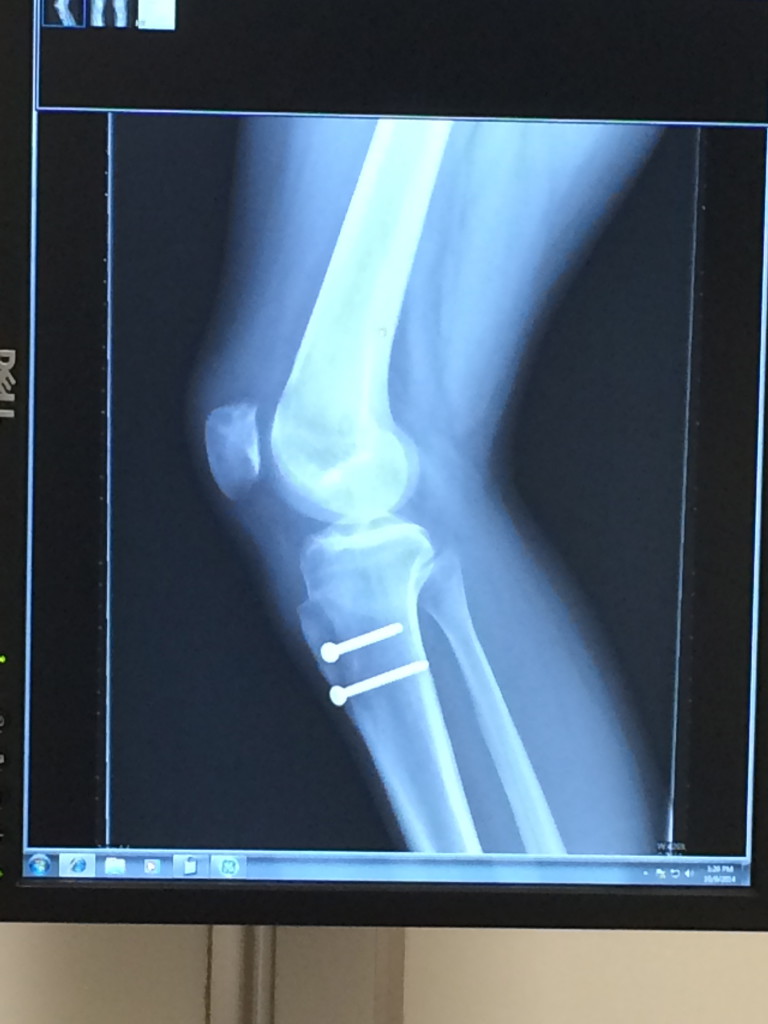

My knee pain was unbearable and the subluxations were becoming more common. I made an appointment to see Dr. Beth Shubin Stein to see what could be done with my knee. After a few appointments, X-rays, and MRIs, we decided to schedule surgery for August 21, 2014. Dr. Shubin Stein performed a TTT and MPFL. A TTT, also known as a tibial tubercle transfer or osteotomy, is a bone-cutting procedure. The top portion of the tibia bone is cut, repositioned, and put in place with two screws. An MPFL, or medial patellofemoral ligament repair, strengthens the medial ligament of the patella to better stabilize it. This was my first surgery and by far, one of the most terrifying experiences I have had.